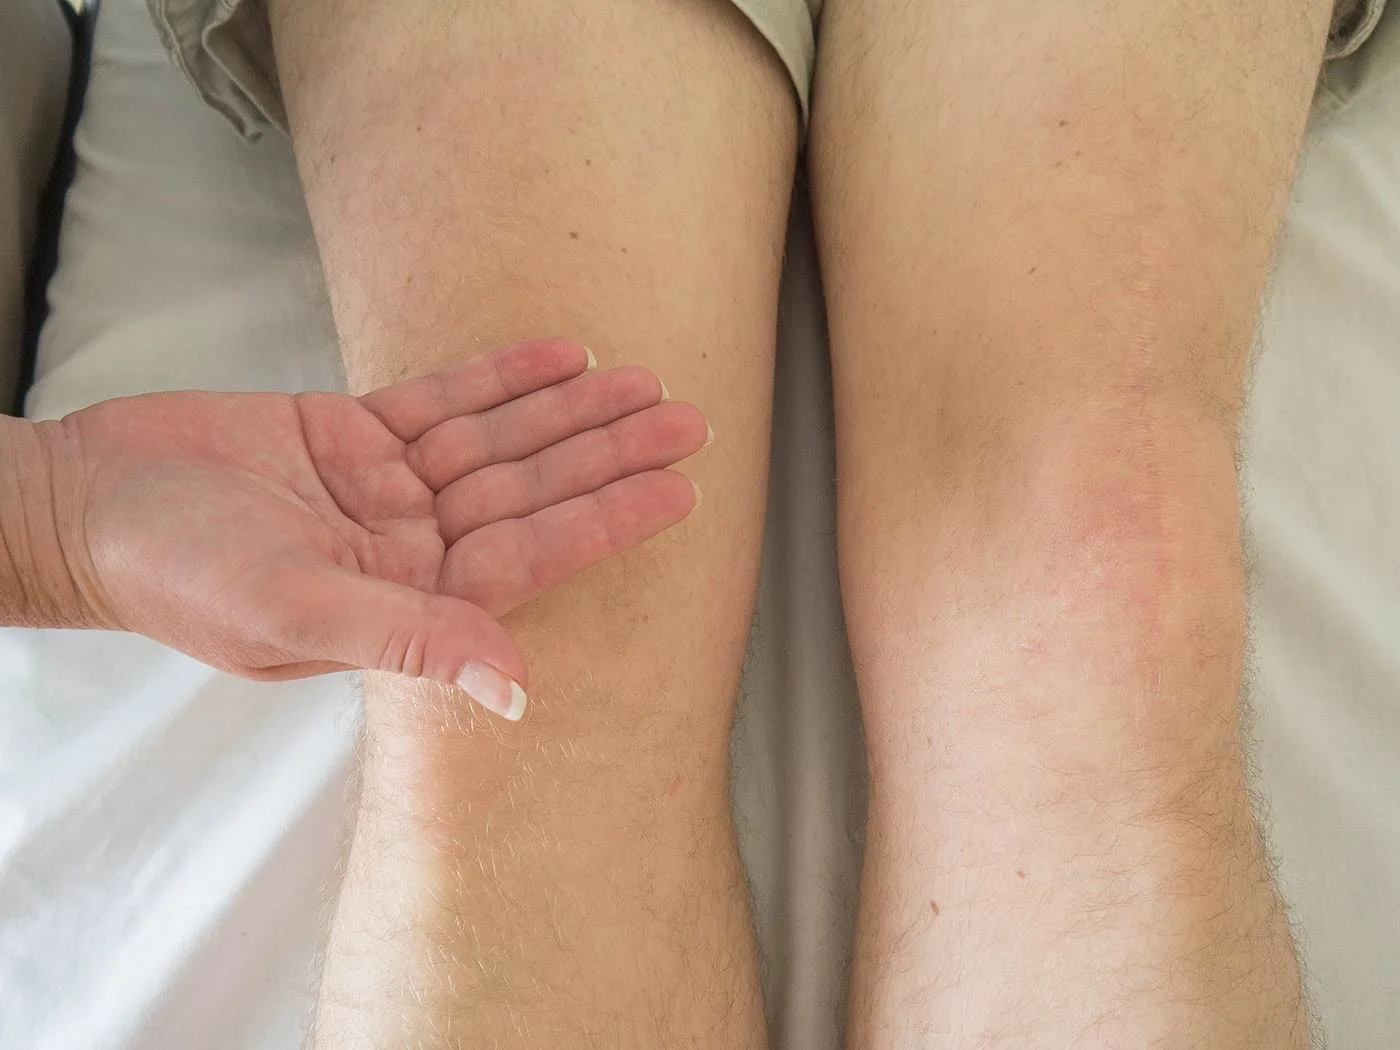

| Compartment Syndrome | Increased pressure within a closed fascial compartment, leading to reduced tissue perfusion, hypoxia, and irreversible muscle and nerve damage. Causes: Fractures (especially tibia/forearm), severe soft tissue trauma, arterial injury, burns, tight casts/dressings, post-ischemic reperfusion swelling, IV fluid extravasation, and bleeding disorders (e.g., hemophilia). High-Risk Notes: Pain may be absent in altered consciousness, children (monitor analgesia response), polytrauma, sedated/epidural cases, or concomitant nerve damage. Open fractures do not always decompress pressure. Gross/Clinical: -tense, shiny leg swelling with blisters in compartment syndrome.Imaging: - Intraoperative fasciotomy | History/Symptoms: Pain out of proportion to the injury (e.g., a “bursting” sensation), which is not relieved by analgesia. Clinical Features (The 5 P’s): - Pain with passive stretch (early, key sign; e.g., ankle dorsiflexion for leg, wrist for forearm). - Paresthesia (early). - Palpable tense swelling (shiny skin, blisters: clear=mild, serosanguinous=severe, bloody=worst; dusky/pallor skin). - Pallor, Paralysis, Pulselessness (late, ominous signs; pulses often palpable until late). Investigations: Primarily a clinical diagnosis (high suspicion key). Compartment pressure measurement can confirm: absolute pressure >30 mmHg or Delta Pressure (Diastolic BP - Compartment P) ≤ 25 mmHg. | Initial: ABCs, supplemental oxygen. Remove all circumferential dressings, casts (bivalve to skin), and splints. Elevate the limb to heart level (not above; higher reduces inflow). Correct any hypotension. Surgical: Urgent Fasciotomy if no response within 1h or confirmed pressure (prophylactic in high-risk like major osteotomy). Release all compartments/skin with long incisions; debride necrotic muscle via 4C’s (early: pink/red, soft, contracts/bleeds on pinch; late: dark, firm, no response); preserve neurovascular. Wound open (bulky dressing/splint, VAC, or boot-lace gradual closure); repeated inspections x48h; coverage in 3-5 days (skin graft usual; flap if nerves/vessels/bone exposed). | Cellulitis, Deep Vein Thrombosis (DVT), Arterial occlusion, Severe soft tissue injury without compartment syndrome; equivocal cases in polytrauma. | Complications: Volkmann’s ischemic contracture (permanent deformity, weakness, sensory loss, chronic pain). Contraindications (Fasciotomy): Confirmed >48h (irreversible damage, high infection risk from dead tissue); crush injuries with already necrotic muscle. |